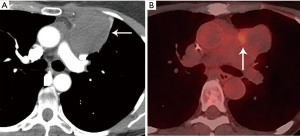

Computed tomography (CT) with contrast is the imaging modality of choice to evaluate thymic tumors due to its high spatial and temporal resolution, ease of access, and convenience. CT can reliably discern location, size/shape, morphology, margins, density, enhancement, and relationship to, or invasion of, adjacent structures (4) (Figure 2). Overall, CT is equal or superior to magnetic resonance imaging (MRI) in the evaluation of mediastinal masses with the caveat that MRI better evaluates thymic cysts or cystic components of tumors (5) (Figure 3).

The role of fluorodeoxyglucose (FDG) positron emission tomography (PET)/computed tomography (CT) in thymic mass evaluation is incompletely defined. False-positive studies can be seen with FDG uptake in non-neoplastic masses, such as in the setting of infection, thymic hyperplasia, or fibrosing mediastinitis. False-negative studies can be seen in certain histological types of thymic malignancy with lower metabolic activity. Additionally, there is lack of technique standardization which results in quantitative variability between studies (8). Given that other prevascular masses such as malignant germ cell tumor and lymphoma are often FDG avid, the presence of a hypermetabolic prevascular mass cannot distinguish between various tumors. There are studies that report that FDG uptake can help predict tumor invasiveness and prognosis. Other studies report FDG uptake as useful in differentiating low-grade from high-grade thymic malignancies; however, other studies report these observations as controversial due to overlapping imaging findings and FDG uptake between low-grade and high-grade thymic tumors (9). Overlapping findings are less common in more aggressive tumors, such as thymic carcinoma, due to higher overall tumor metabolism, with studies reporting that a maximum standard uptake value (SUVmax) of 6 can serve as a cutoff between thymic carcinoma and lower grade thymic tumors (10) (Figures 2,3). However, this threshold cannot differentiate thymic carcinoma from other malignancies such as lymphoma or non-seminomatous germ cell tumor. Finally, PET/CT clearly has a role to detect occult metastasis in hypermetabolic tumors.

Thymoma typically presents as a smooth or lobular mass involving one lobe of the thymus, although bilateral involvement can occur (39). Most thymomas demonstrate homogeneous enhancement, although, approximately one third can be heterogeneous due to areas of hemorrhage, necrosis, cystic change, or calcification (1) (Figures 8,9). Imaging characteristics can vary according to WHO histological classification, with vascular invasion and pleural/pericardial involvement more common with more aggressive histology (Figure 2). The thymomas with the more aggressive histologies tend to be larger, more lobular or irregular, have cystic or necrotic change, areas of calcification, or evidence of infiltration into surrounding fat (40-42) (Figure 10).

The role of FDG PET/CT in thymoma imaging is limited. Given the presence of FDG uptake in the normal and hyperplastic thymus, especially in younger adults and children, false-positive results can occur. In fact, physiologic uptake has been reported in 28% of patients under 40 years of age and up to 73% in children less than 13 years of age (44). PET/CT has not been shown to differentiate different WHO histological classifications of thymic tumors, although the more aggressive histologies tend towards higher FDG uptake (45,46) (Figures 2,3). Indium111 octreotide nuclear medicine scans have now been replaced by 68Ga-labeled somatostatin analogues because 68Ga-labeled somatostatin analogues, such as 68Ga-DOTATATE, are used for PET/CT, and thus provide better resolution.

Thymic carcinoma and thymic neuroendocrine tumors have similar imaging characteristics which may often overlap with the more aggressive histologies of thymoma, such as B3 thymoma. Thymic carcinomas and neuroendocrine tumors commonly present as large prevascular masses with irregular or poorly marginated borders, areas of necrosis or cystic change, and hemorrhage. Compared with thymomas, there is a greater incidence of local invasion (1) (Figures 2,11). Pleural or pericardial nodules, pleural effusion, and distant metastasis are more commonly seen with thymic carcinoma or thymic neuroendocrine tumor than thymoma (Figure 12). More aggressive thymic epithelial tumors can invade or compress the SVC resulting in SVC syndrome. This is a clinical syndrome marked by swelling of the neck, face, and upper extremities, with associated cough, headache, and shortness of breath. Pleural metastatic disease, which is more common in thymic carcinoma and thymic neuroendocrine carcinoma, generally consists of small enhancing pleural nodules or areas of enhancing pleural thickening. These are generally adequately assessed with thin-slice contrast-enhanced CT, although, contrast-enhanced MRI and PET/CT can be of additional benefit in questionable cases.

As noted, FDG PET/CT does not reliably differentiate between the different histological types of thymoma. Several small studies, however, have suggested that FDG PET/CT can help differentiate thymoma from thymic carcinoma using various cutoffs of SUV max ranging between 4.6 and 6.3 (49,50). Since the more aggressive tumor histologies are FDG avid, FDG PET/CT can be useful in the assessment and follow-up of thymic carcinoma but is not routinely recommended (51). Thymic neuroendocrine tumors can additionally be evaluated with 68Ga-DOTATATE PET/CT which may demonstrate improved sensitivity for lesion detection compared with FDG PET/CT which can help identify tumors that are candidates for peptide receptor radiotherapy (PRRT) with 177Lutetium (51).